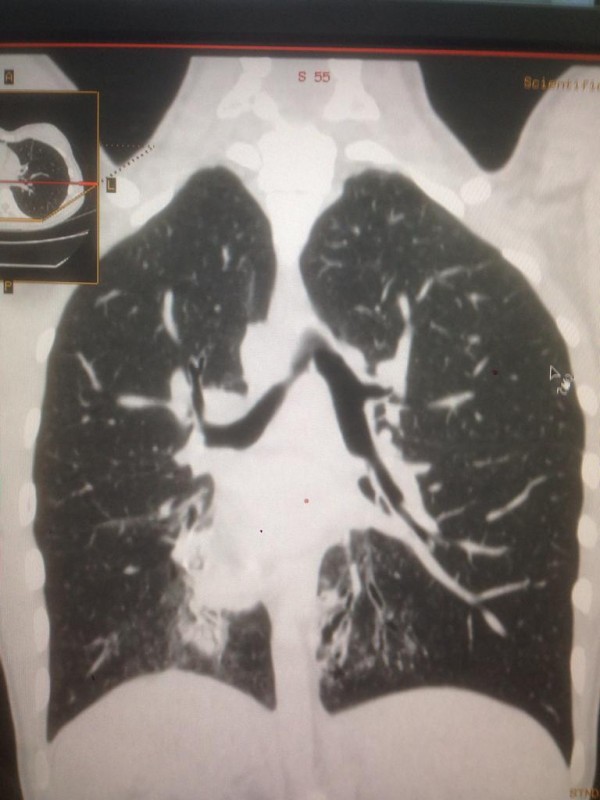

Также зеркальное расположение внутренних органов встречается при синдроме Зиверта-Картагенера, это аутосомно-рецессивное генетическое заболевание. Его коэффициент один случай из 50 тысяч человек. В настоящее время в Казахстане на учете с такой патологией состоят 16 детей.

"Это генное нарушение. При нем у людей нездоровы дыхательные пути. Характерные черты: синклиты, бронхоэктазы и зеркальное расположение органов. Люди с таким диагнозом испытывают слабость, температуру, боль в ушах, одышку, хрипы. Поэтому пациенты с раннего возраста проходят лечение. Состоят на диспансерном учете у детского пульмонолога. В год они получают около пяти раз стационарное лечение, находятся под наблюдением врачей, пропивают антибиотики", - говорит собеседник.

Синдром Зиверта-Картагенера. Снимок предоставлен Сундетом Саргеловым